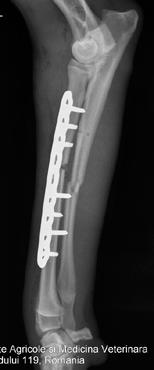

Timpii operatori în MIPO au fost: reducerea indirectă a fracturii, realizarea inciziilor proximal ș i distal de focarul de fractură, crearea unui tunel epiperiostal între cele două incizii (este important ca periostul să rămână intact), glisarea plăcii între cele două incizii create anterior, fixarea plăcii la os cu ș uruburi (inserarea a 2 ­ 3 ș uruburi la fiecare capăt al plăcii) ș i sutura inciziilor operatorii (fig. 1).

Pentru monitorizarea postoperatorie a vindecării osoase s ­ a utilizat instalația radiologică tip Multix Swing (Siemens GmbH), cu procesarea imaginilor prin intermediul sistemului de radiografie computerizată (CR) Direct View Vista CR (Caresteam) și aplicația software AQS Vet Standalone (Arzt+Praxis GmbH). Incidențele au fost cele convenționale (figura 2). Parametrii radiologici utilizați au fost: humerus ­ 50

Figura 1. Pregătirea sălii de operaţie pentru rezolvarea unei fracturi cominutive diafizare de tibie stângă la un metis de 2 ani prin MIPO (A). Accesul minim invaziv la os (B). Fixarea plăcii (C)

kV, 28 mA, radius ­ 48 kV, 28 mA, femur ­ 52 kV, 28 mA și tibie ­ 48 kV, 28 mA.

Pentru cei 18 pacienți operați, doar 12 proprietari au fost consecvenți la controlul radiografic propus pentru monitorizarea stadiilor de vindecare. Din cei 12 câini, doi au prezentat complicații, respectiv o întârzire în vindecare și un eșec de stabilizare cu prezența osteolizei în jurul șuruburilor (cazul 112/08.03.2012) ­ figura 5.

Zece pacienți au fost monitorizați și investigați imagistic, evaluându ­ se la interval de două săptămâni (cu o întârziere de maxim trei zile) timp de trei luni. În tabelul 3 este redată analiza statistică a frecvențelor stadiilor de vindecare (IBM SPSS Statistics 20) pentru perioada de 12 săptămâni postoperator.

La două săptămâni postoperator, uniunea fracturii nu a avut loc la nici un pacient. La șase câini, linia de fractură a fost încă prezentă, fără formare de calus sau doar cu urme de calus. La patru câini, s ­ a observat o aparentă punte de calus care traversează linia de fractură perceptibilă încă.

În săptămâna a 10 și a 12 postoperator, uniunea a fost prezentă la toți pacienții, observându ­ se linia de fractură obliterată și structura osoasă omogenă, cu excepția unui singur pa ­